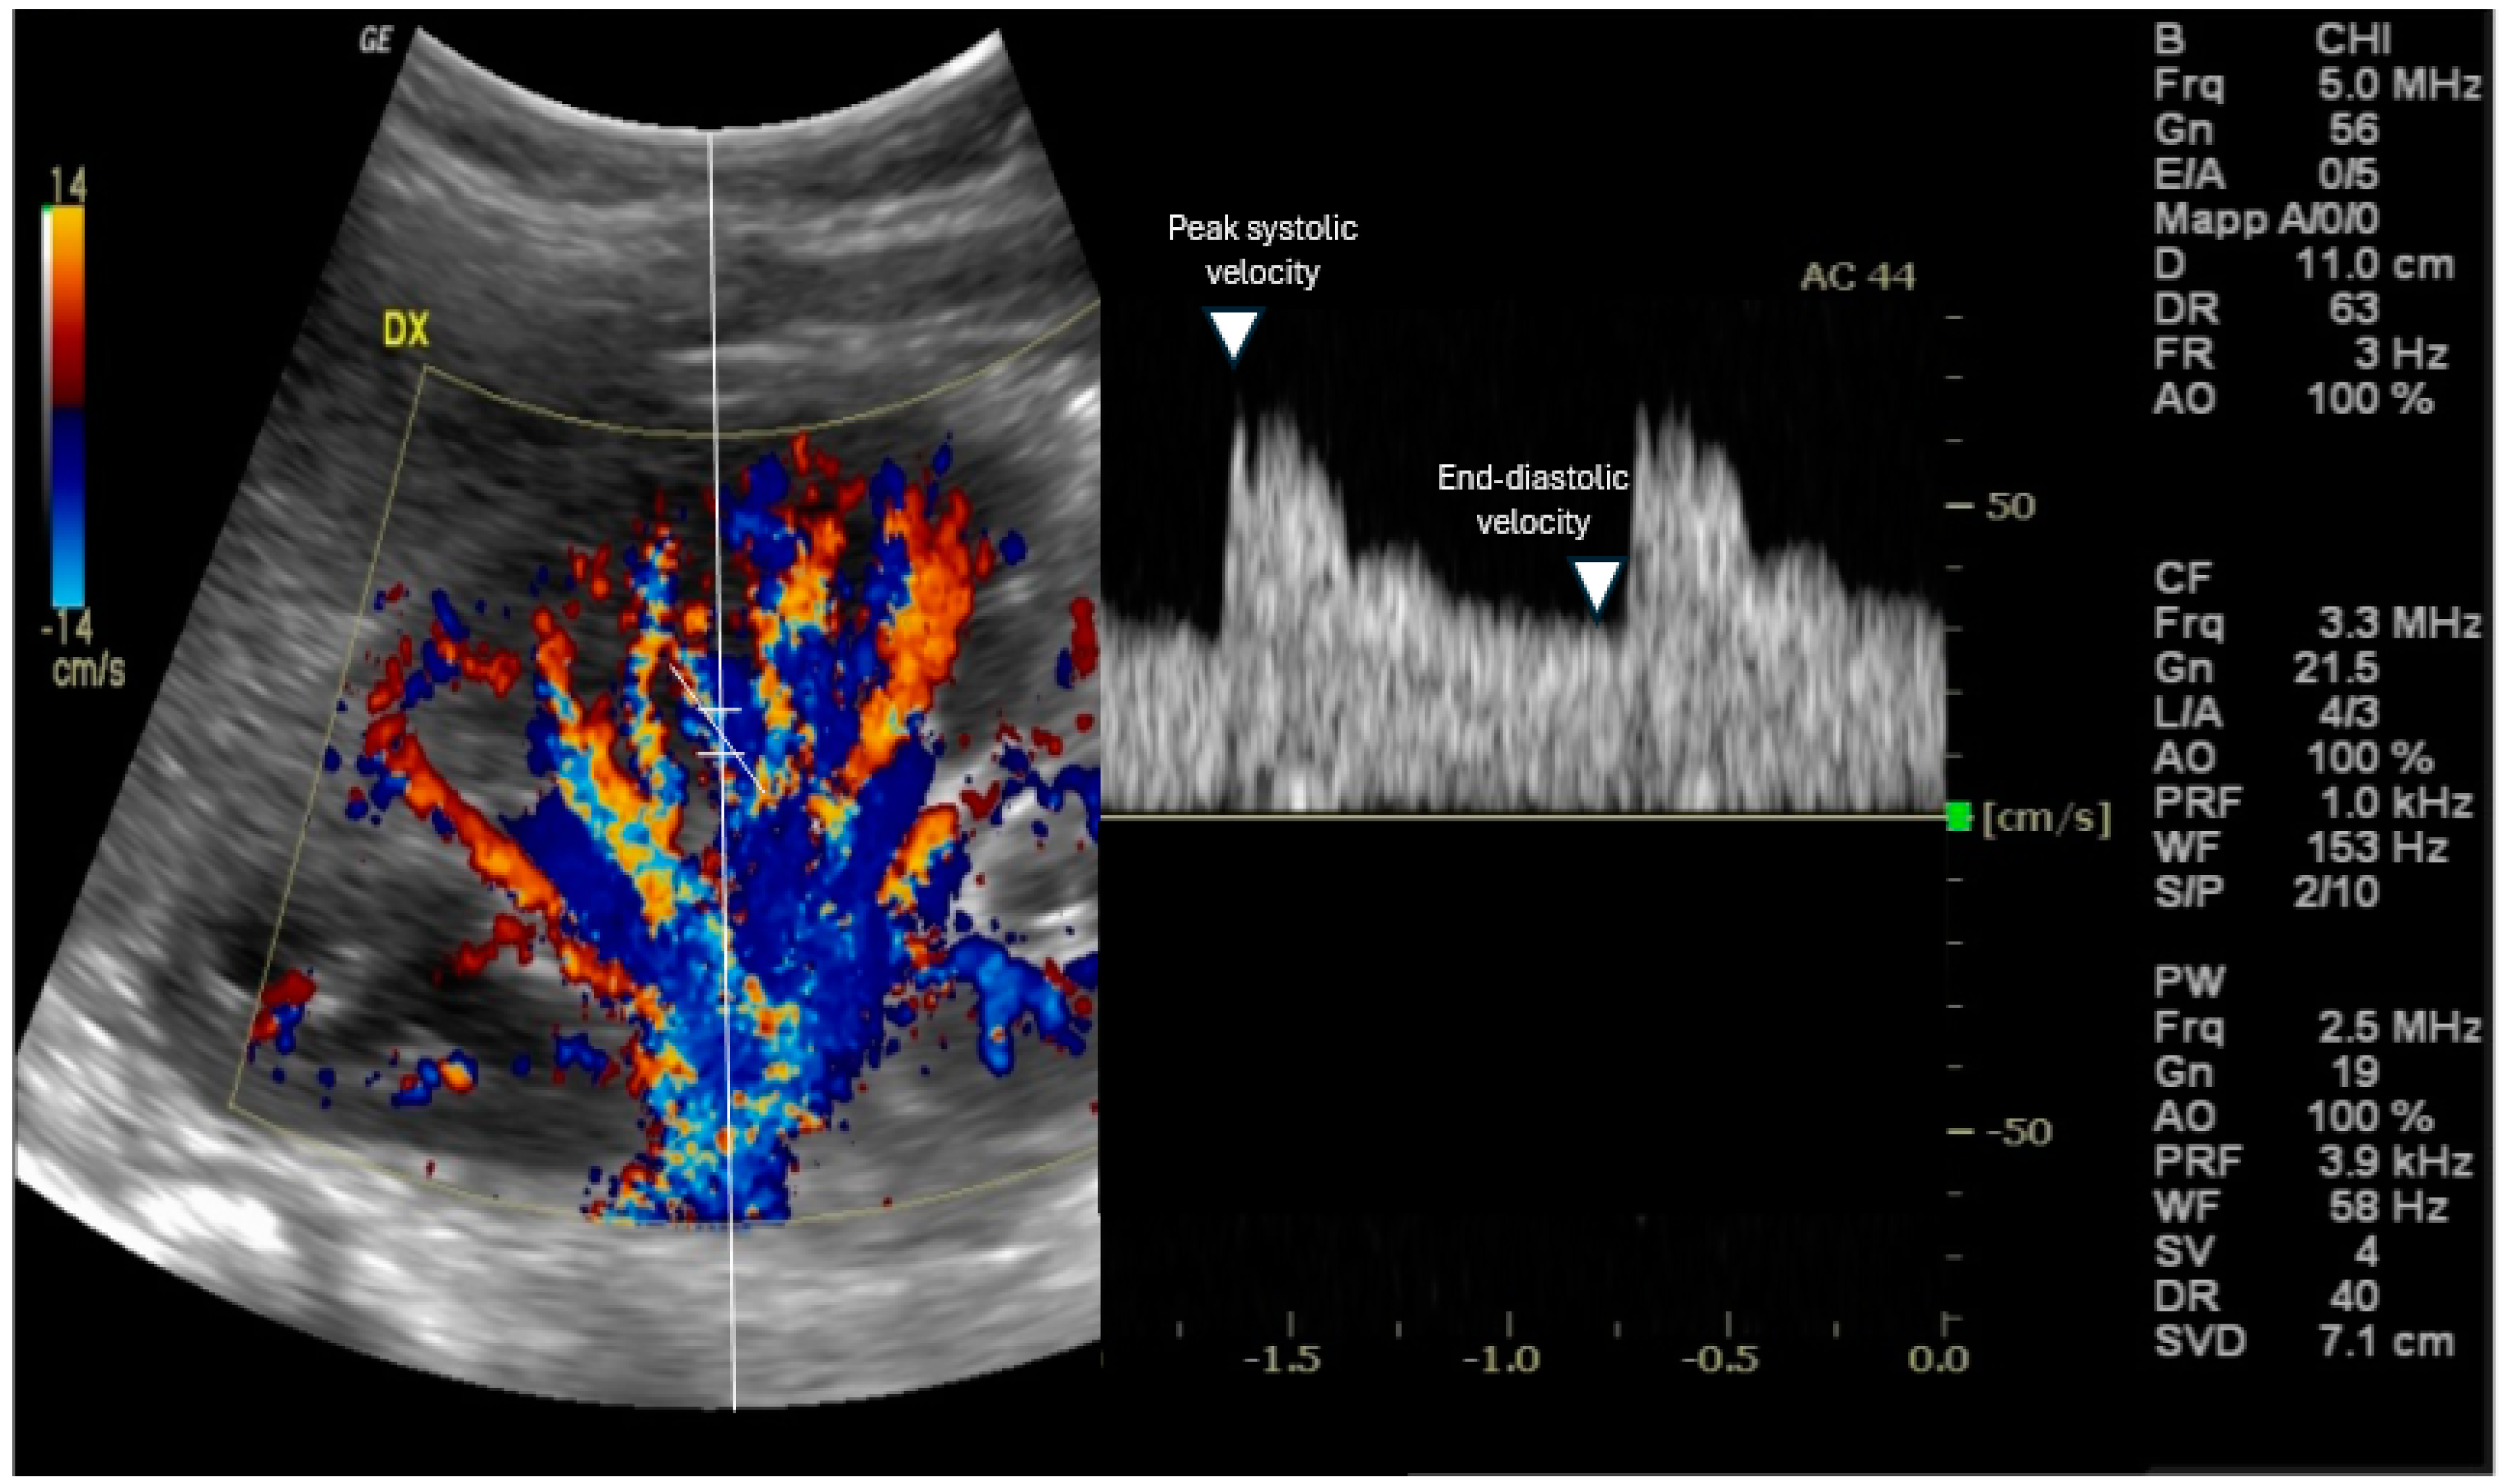

2. Measuring RRI: Methodology

- Skills: RRI measurement needs a trained operator [13] to achieve precise and repeatable results.

- Standardized ultrasound machine settings, including Doppler gain, pulse repetition frequency, and wall filter should be used to minimize variability [14].